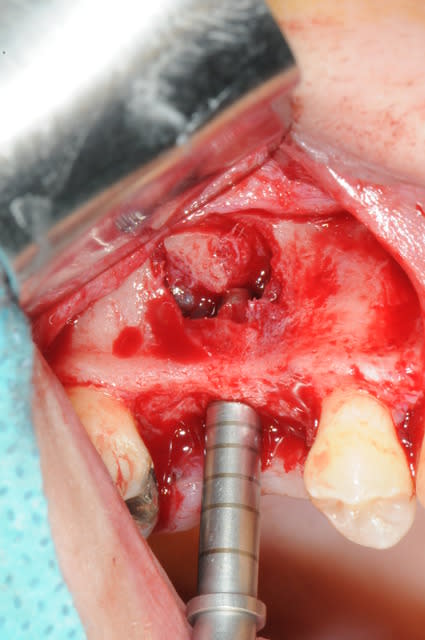

le sujet tombe à pic!

je viens de faire un sinus lift ce matin;

- 3 à 4 mm de hauteur sous sinusienne

- des cloisons de refend partout

- comblement avec du Vital Os

- un implant Axiom D4 L 10

comme je n'avais pas le temps de faire des photos la dernière fois et que j'en étais frustré, je me suis un peu lâcher aujourd'hui...

les premières photos, c'était ouverture par voie latérale